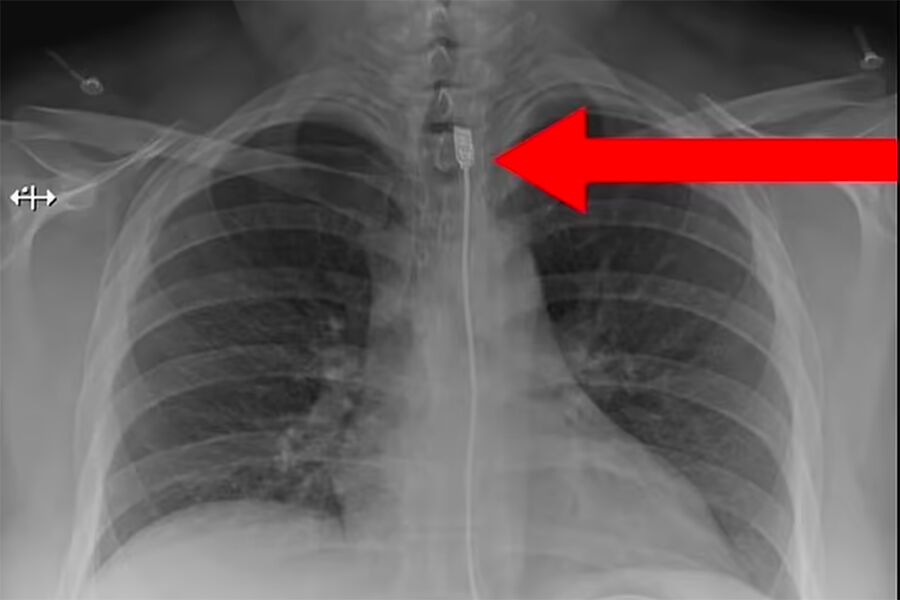

Обследование показало, что кабель застрял в пищеводе пострадавшей, поэтому медикам пришлось провести специальную процедуру, чтобы достать посторонний предмет. После операции женщина была переведена в реанимацию, а потом отпущена домой.